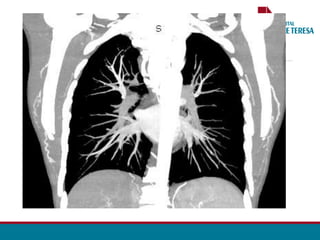

ANGIO TOMOGRAFIA

• Segmento estenosado

• Circulação colateral

• Planejamento cirúrgico

•Acompanhamento pós - OP